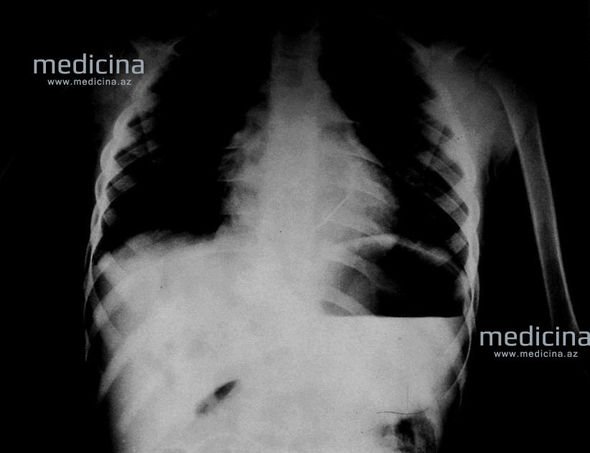

Elmi-Tədqiqat Pediatriya İnstitutuna gətirilən uşağı cərrah Gündüz Ağayev müayinə edib. 5 yaşlı qızın ürəyində sağ mədəciyin divarında ürəklə birgə pulsasiya edən iynə aşkar olunub və ürəyin yad cismi diaqnozu qoyulub.

G. Ağayevin sözlərinə görə, əməliyyatdan öncə müəyyən edilib ki, iynə ürəyi 2 mm zədələyib və artıq qanama başlayıb.